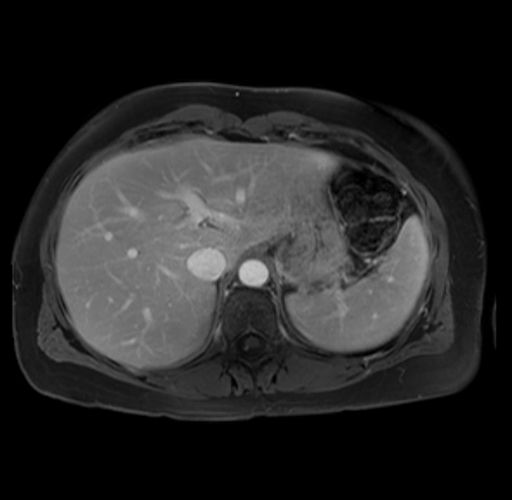

Imaging Analysis

Look through the patient's CT scan to identify any areas of concern for the necessary procedure.

Based on your CT findings, which issue(s) are present and would give reason for "planned slowing down moment(s)" in this case?